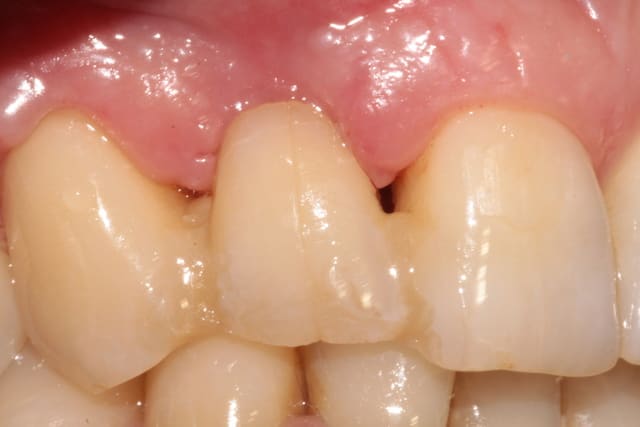

la suite 6 mois plus tard

photo 3 reconstruction avec le pilier en place

photo 4 vue occlusale de l'implant et de la reconstruction osseuse obtenue